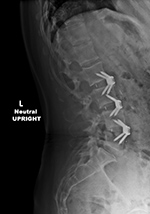

| Zero-Profile lumbar fixation L2-L4 |

| 45 year-old woman with L2-5 anterior lumbar interbody fusion (ALIF) for low back pain. |